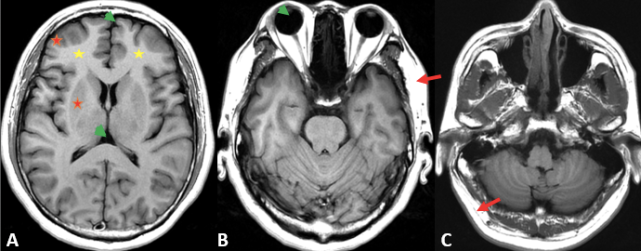

图 1. T2WI 上脑白质呈稍低信号(黄色星);脑灰质(皮层和灰质核团)呈稍高信号(红色星);脑脊液及玻璃体呈明显高信号(绿色箭头);颅内大血管(静脉窦、大脑中动脉及基底动脉)流空信号,呈低信号(红色箭)

图 5. A. T2 FLAIR 灰白质对比差(红色星和黄色星);脑脊液、玻璃体及病变内囊性成份(自由水)呈明显低信号(绿色箭头);B. 为同层面的 T2 FLAIR 和 T2WI 显示病变周围水肿(结合水)仍呈稍高信号(红色箭);C. 冠状位为 T2 FLAIR